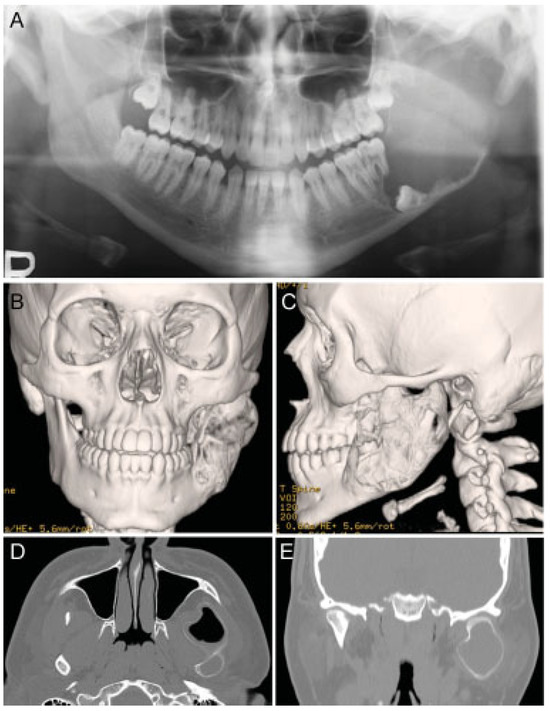

Two Stage Enucleation and Deflation of a Large Unicystic Ameloblastoma with Mural Invasion in Mandible

Case Report